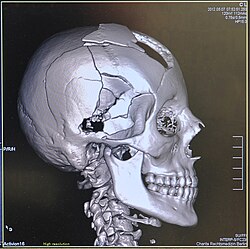

Head

CT scanning of the head is typically used to detect infarction (stroke), tumors, calcifications, haemorrhage, and bone trauma.[32] Of the above, hypodense (dark) structures can indicate edema and infarction, hyperdense (bright) structures indicate calcifications and haemorrhage and bone trauma can be seen as disjunction in bone windows. Tumors can be detected by the swelling and anatomical distortion they cause, or by surrounding edema. CT scanning of the head is also used in CT-guided stereotactic surgery and radiosurgery for treatment of intracranial tumors, arteriovenous malformations, and other surgically treatable conditions using a device known as the N-localizer.[33][34][35][36][37][38]